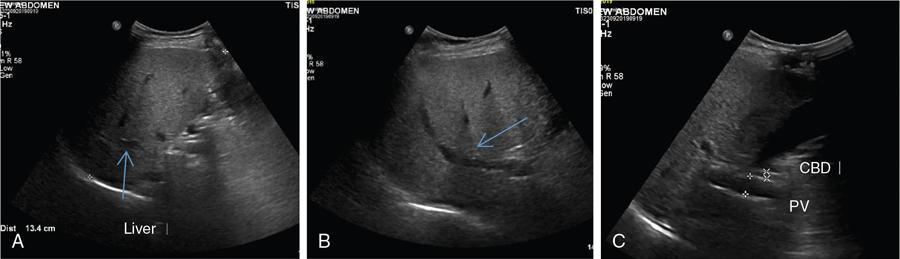

Excessive triglyceride accumulation within hepatocytes is defined as hepatic steatosis. Major conditions associated with hepatic steatosis include alcoholic fatty liver disease (AFLD) and nonalcoholic fatty liver disease (NAFLD). Causes of hepatic steatosis are discussed in Table 9.10.3. NAFLD is the most common form of hepatic steatosis and discussed in detail below. Up to 90% of patients with chronic alcoholic intake have fatty liver. Those with pure AFLD have a 10% risk of progressing to cirrhosis. Consumption of 30 g ethanol/day shows increased risk of chronic liver disease and cirrhosis. Other risk factors include female sex, obesity, cigarette smoking, obesity and associated risk factors. These factors are divided into 2 main categories which can cause fatty liver: inborn errors of metabolism and acquired metabolic disorders. Inborn errors of metabolism include abetalipoproteinemia, galactosemia, glycogen storage disease, hereditary fructose intolerance, homocystinuria and Wilson disease. Inflammatory bowel disease, jejunoileal bypass, malnutrition, starvation and total parenteral nutrition are acquired metabolic factors associated with increased risk. Chronic HCV infection, is associated with hepatic steatosis, with prevalence of 40%–80%. Hepatic steatosis can be seen as an adverse reaction to some medications such as tetracycline, valproic acid, some of chemotherapeutic agents, dexamethasone, amiodarone, methotrexate, tamoxifen and acetylsalicylic acid. Either microvesicular or macrovesicular steatosis can be observed in drug-induced hepatic steatosis. It generally occurs with therapy lasting several weeks or months and is reversible after discontinuation. The leading cause of hepatic steatosis in paediatric population is NAFLD. Six per cent of these patients develop cirrhosis and end-stage disease. Other less common causes include starvation and malnutrition, drugs (glucocorticoids, oestrogens, tetracyclines, and methotrexate), intoxications (carbon tetrachloride, organic phosphates, organic solvents, and alcohol), metabolic disorders, hepatitis C infection, and total parenteral nutrition. NAFLD is defined as steatosis affecting >5% of hepatocytes in the absence of a secondary cause. NAFLD represents a spectrum of disease, ranging from simple steatosis to steatohepatitis through to fibrosis and cirrhosis and in some cases hepatocellular carcinoma. NAFLD is a growing epidemic worldwide in part due to obesity and insulin resistance leading to liver accumulation of triglycerides and free fatty acids. Nonalcoholic steatohepatitis (NASH) is defined by histologic terms as a necroinflammatory process whereby the liver cells become injured in a background of steatosis. 20% of patients with NAFL progress to NASH, which progresses to fibrosis and cirrhosis over a 15-year time period (Fig. 9.10.3). The definition of NAFLD requires imaging or histology evidence of steatosis and no causes for secondary hepatic fat accumulation like significant alcohol intake, drugs or hereditary disorders (Table 9.10.4). The incidence of NAFLD ranges from 20% to 30% in Western countries and 5%–18% in Asia. As it currently stands, NAFLD represents the second most common reason to be listed for a liver transplant. The prevalence of NAFLD is higher in patients with obesity, diabetes, and patients with hyperlipidaemia. Prevalence increase with age from less than 20% at age 20 to more than 40% over 60 years of age. Males show a higher risk for progression to NASH and fibrosis (Table 9.10.5). Up to 90% of patients with NAFLD have simple steatosis, and about 30% of patients with NAFL develop NASH, and in again about 30%–40% of NASH patients the disease progresses to manifest fibrosis and cirrhosis NAFLD related cirrhosis has a 10-year mortality of 25% and a 5% chance of developing end-stage liver disease and HCC. The theory implicated in the pathogenesis of NAFLD is the two-hit theory. Insulin resistance, enhanced dietary influx and increased hepatic lipogenesis leading to accumulation of triglycerides (TG) and FFA in the hepatocytes is the first hit. The lipid peroxidation, mitochondrial dysfunction and inflammation resulting in hepatocyte damage and development of liver fibrosis is the second hit. The stages of NAFLD on histology range from steatosis initially to hepatic fibrosis in late stages. In the steatotic stage large (macro-) and small (micro-) vesicles of fat, predominately triglycerides, accumulate within hepatocytes. The affected parenchyma is divided into thirds: 5%–33%, 34%–66% and >66% and graded as mild, moderate and respectively. Ballooned hepatocytes with accompanied steatosis and inflammation are characteristic of the steatohepatitis stage. Fibrosis has a characteristic appearance with early lesions showing a perisinusoidal deposition followed by periportal fibrosis which progresses to bridging. Raised GGT is the most common liver enzyme elevated in NAFLD. Transaminases are within normal range in 80% patients. No specific blood tests can diagnose NAFLD. Liver biopsy has remained the gold standard for diagnosis and quantification of liver fat. Drawbacks, however, include invasive nature, sampling error and procedure related complications like bleeding. Various imaging techniques are currently available in diagnosing and quantifying liver fat. MRI in particular proton density imaging and MR Spectroscopy have revolutionized imaging of fatty liver. Normal liver parenchyma is the same as or slightly more echogenic than the adjacent kidney and spleen. Fat deposition leads to increased echogenicity of liver. Decreased beam attenuation in patients with fatty change leads to poor visualization of structures such as intrahepatic vessels, bile ducts and liver lesions and in severe cases diaphragm (Table 9.10.6). Fatty liver can be graded on USG as: US has a fair accuracy of detecting the moderate to severe hepatic steatosis with sensitivity of about 90% and specificity of about 95% for patients without concomitant chronic liver disease. Ultrasound is observer and equipment dependent. Confounding factors such as large body hiatus may lead to overestimation of hepatic steatosis due to beam attenuation by overlying fat. Conditions like fibrosis, inflammation can affect interpretation. The ratio between the mean brightness level of liver and right kidney is called the Hepatorenal sonographic index. A cut off of 1.49 has a high sensitivity and specificity for diagnosis of steatosis >5%. The main advantages of CT for assessing steatosis are relatively fast acquisition, ease of performance, and quantitative results. Estimation of fatty liver is done on non-contrast enhanced images. The normal liver density is around 60 HU, which is approximately 10 HU higher than normal spleen. Fat accumulation in the liver manifests as proportionate decrease in density. Both the absolute and relative (to the spleen) values are used to characterize steatosis; a cut-off value of 40 HU has been suggested to predict fat content greater than 30% (Figs. 9.10.6 and 9.10.7) Attenuation difference between liver and spleen on unenhanced CT scan is a commonly used quantitative parameter to evaluate hepatic steatosis. This avoids errors in attenuation value measurement from different CT scanners and different reconstruction algorithms. Normal liver parenchymal attenuation on nonenhanced CT is slightly higher than the spleen. Liver attenuation progressively decreases as percentage steatosis increases (Table 9.10.7) (Fig. 9.10.8) Methods of liver fat quantification on CT have been discussed in details in chapter on liver transplant. Limited diagnostic accuracy for detecting mild degree hepatic steatosis is one of major drawback of CT. Disorders causing hyperdensity of liver such as iron, glycogen deposition can lead to errors in interpretation. The concomitant presence of iron and fat may not be accurately diagnosed on CT. Low CT density values may also be caused by oedema and inflammation. Likewise, the spleen is an imperfect reference standard as it can be affected by haemosiderosis and haemochromatosis in a small minority of patients. Dual-energy CT with its ability to perform material decomposition is more accurate in quantifying hepatic steatosis and allows staging of fibrosis. Imaging is done with two different energies (typically 80 kVp and 140 kVp). DECT has the potential to quantitate liver fat content independent of ROI (region of interest) placement. Magnetic resonance imaging (MRI) is presently the most accurate imaging modality for the evaluation of hepatic steatosis. Several different methods have been developed and introduced in MRI for the evaluation of hepatic steatosis. In this technique typically, two gradient echoes are acquired, one employing a TE in which the water peak (4.7 ppm) and the dominant fat peak (1.3 ppm) are ‘out of phase’ and hence subtractive (SOP), and the other using a TE in which the two peaks are ‘in phase’ and therefore additive (SIP). Because two echoes are acquired, this is often called ‘dual-phase’ or ‘dual echo’ imaging. Fat Signal Percentage is calculated as [SIP – SOP]/[2 × SIP] ×100. The dynamic range of magnitude based chemical shift techniques has typically a 0%–50% signal fat-fraction (Fig. 9.10.9) This technique uses both magnitude and phase information from three or more images acquired at different echo times appropriate for more accurate separation of water and fat signals as against only magnitude information in dual-echo. These methods provide estimates of fat fraction with a dynamic range of 0%–100%. Proton density Fat fraction (PDFF) is calculated as Sf/(Sw + Sf) where Sw = SI of the water component, Sf = SI of the fat component. PDFF specifically reflects the concentration of triglycerides in the hepatocytes as lipids within the other structures such as cell membranes and organelles are occult. Sensitivity up to 96% and specificity up to 100% for detecting any degree of steatosis have been reported. A fat-fraction threshold of 5.56% is commonly used to define steatosis; however, the optimal cut-off value still needs to be defined (Figs. 9.10.10 and 9.10.11). MRS can directly measure the chemical composition within tissue based on the frequency composition of the signal originated from the voxel of interest. Water proton peak appears as a single peak at 4.7 ppm, whereas fat peaks appear as multiple peaks around 1.3 ppm. PDFF can be calculated as the ratio of the sum of the signal intensities derived from the protons in fat divided by the sum of the signal intensities originated from the protons in both fat and water (Fig. 9.10.12). TABLE 9.10.8 MRS data are usually obtained from a single voxel manually placed in the liver parenchyma usually right posterior segment of the liver. Reported MRS sensitivities and specificities for detection of mild hepatic steatosis are 80.0%–91.0% and 80.2%–87.0%, respectively, outperforming CT and US. MRS can also provide excellent reproducibility of measurement. It is also unaffected by confounding factors like fibrosis, iron overload and glycogen. Small sample volume usually less than 3 × 3 × 3 cm3 is a major limitation of MRS, particularly in patients with uneven fatty change. Despite these practical limitations, MRS is considered to be the gold standard MR method for hepatic fat quantification. This is the most frequently encountered pattern and considering the homogenous involvement poses no diagnostic dilemma. Focal fat deposition and focal sparing in diffuse fatty liver are less common. These usually occur in specific locations like adjacent to falciform ligament or ligamentum venosum, in portal hepatis or gallbladder fossa. Imaging findings are suggestive of fatty pseudolesions rather than true masses. Occurrence in characteristic locations, absence of mass effect on vessels and structures, geographic configuration and contrast enhancement similar to or less than adjacent liver (Fig. 9.10.13). Fat deposition around insulinoma metastasis can occur as a local effect of insulin on the liver parenchyma. On ultrasound, it appears as an echogenic rim shows signal drop on out of phase images. Eisenberg has reported perilesional steatosis around focal nodular hyperplasia. Sometimes multiple small foci and seen scattered throughout the liver. These may appear as small round nodules (Fig. 9.10.14). Opposed phased imaging is more useful than CT or US to establish diagnosis. These may, however, pose a diagnostic dilemma in patients with known malignancy. Perivascular fatty infiltration is a recently described entity, mostly seen in alcoholic patients. This pattern is characterized by halos of fat that surround the hepatic veins, the portal veins, or both hepatic and portal veins (Fig. 9.10.15). Normal vessels coursing through the lesion without attenuation in calibre suggest the diagnosis. Peritoneal dialysis with insulin in the dialysate in patients with renal failure and insulin-dependent diabetes. Exposure of subcapsular hepatocytes to a higher concentration of insulin results in fat deposition in the subcapsular regions. Some hepatic lesions such as hepatic adenoma, hepatocellular carcinoma, regenerative nodules and focal nodular hyperplasia can show intracellular steatosis (Fig. 9.10.16). These areas show signal drop on opposed phase. However, postcontrast imaging characteristics of these lesions allow differentiation from areas of focal steatosis. Perilesional sparing has been reported in haemangioma and hepatocellular carcinomas. This may mainly represent decreased portal flow due to either compressed or atrophic hepatocyte cords in expanding metastases or arterioportal perfusion abnormalities in haemangiomas. The differential diagnosis of focal fat infiltration is discussed in Table 9.10.9. Accurate history and chemical shift imaging showing signal drop help in differentiation of focal fat from metastasis. These are visible only during the arterial and portal venous phases after contrast agent administration. The morphologic appearance of fat deposition and perfusion abnormalities is similar. Perfusion abnormalities however are visible only during the arterial and portal venous phases (Fig. 9.10.17). They are not seen as an attenuation difference on nonenhanced CT. Periportal oedema, inflammation, haemorrhage and lymphatic dilatation may mimic perivascular fat. With the exception of haemorrhage all other conditions affect periportal region symmetrically (Fig. 9.10.18). Patients with haemorrhages may show other signs of injury. Chemical shift imaging is helpful in cases with diagnostic challenges.

USG

Ultrasound is accurate for a diagnosis of >20%–30% steatosis, that is, moderate and severe cases but is poorly sensitive for mild steatosis

Grading of liver steatosis by ultrasound (Qualitative)

Operator – and equipment – dependent and has substantial intra- and interobserver variability

Disadvantages

Hepatorenal sonographic index